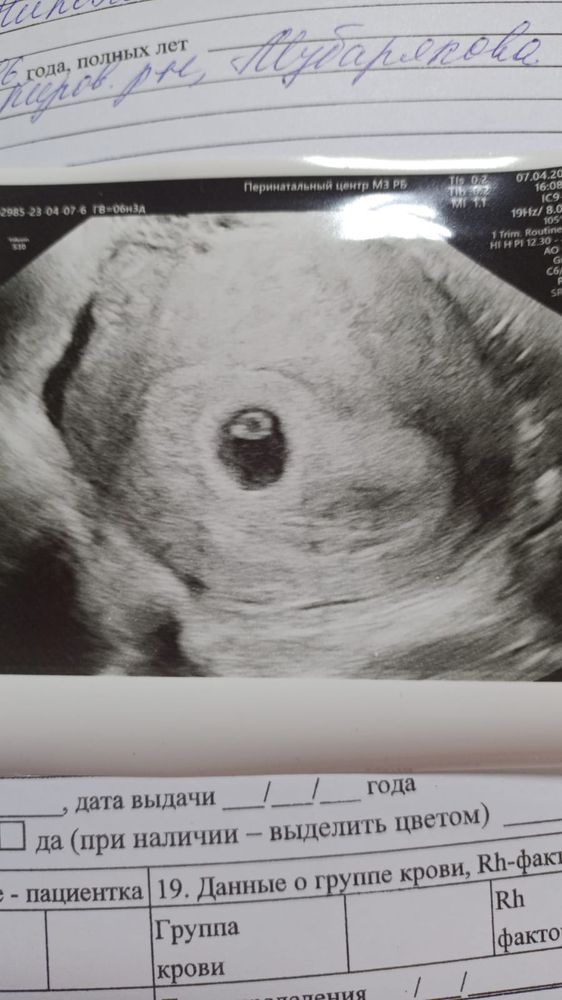

Вчера на УЗИ наконец то увидели моего головастика и даже послушали сердечко ❤️ узистка сказала что на этом сроке эмбрион называют кольцо с бриллиантом 😃а вам так говорили?(на первых двух УЗИ не видели из за маленького срока)

Тоже вчера были на УЗИ, в описании в виде перстня на желточном мешочке🤗